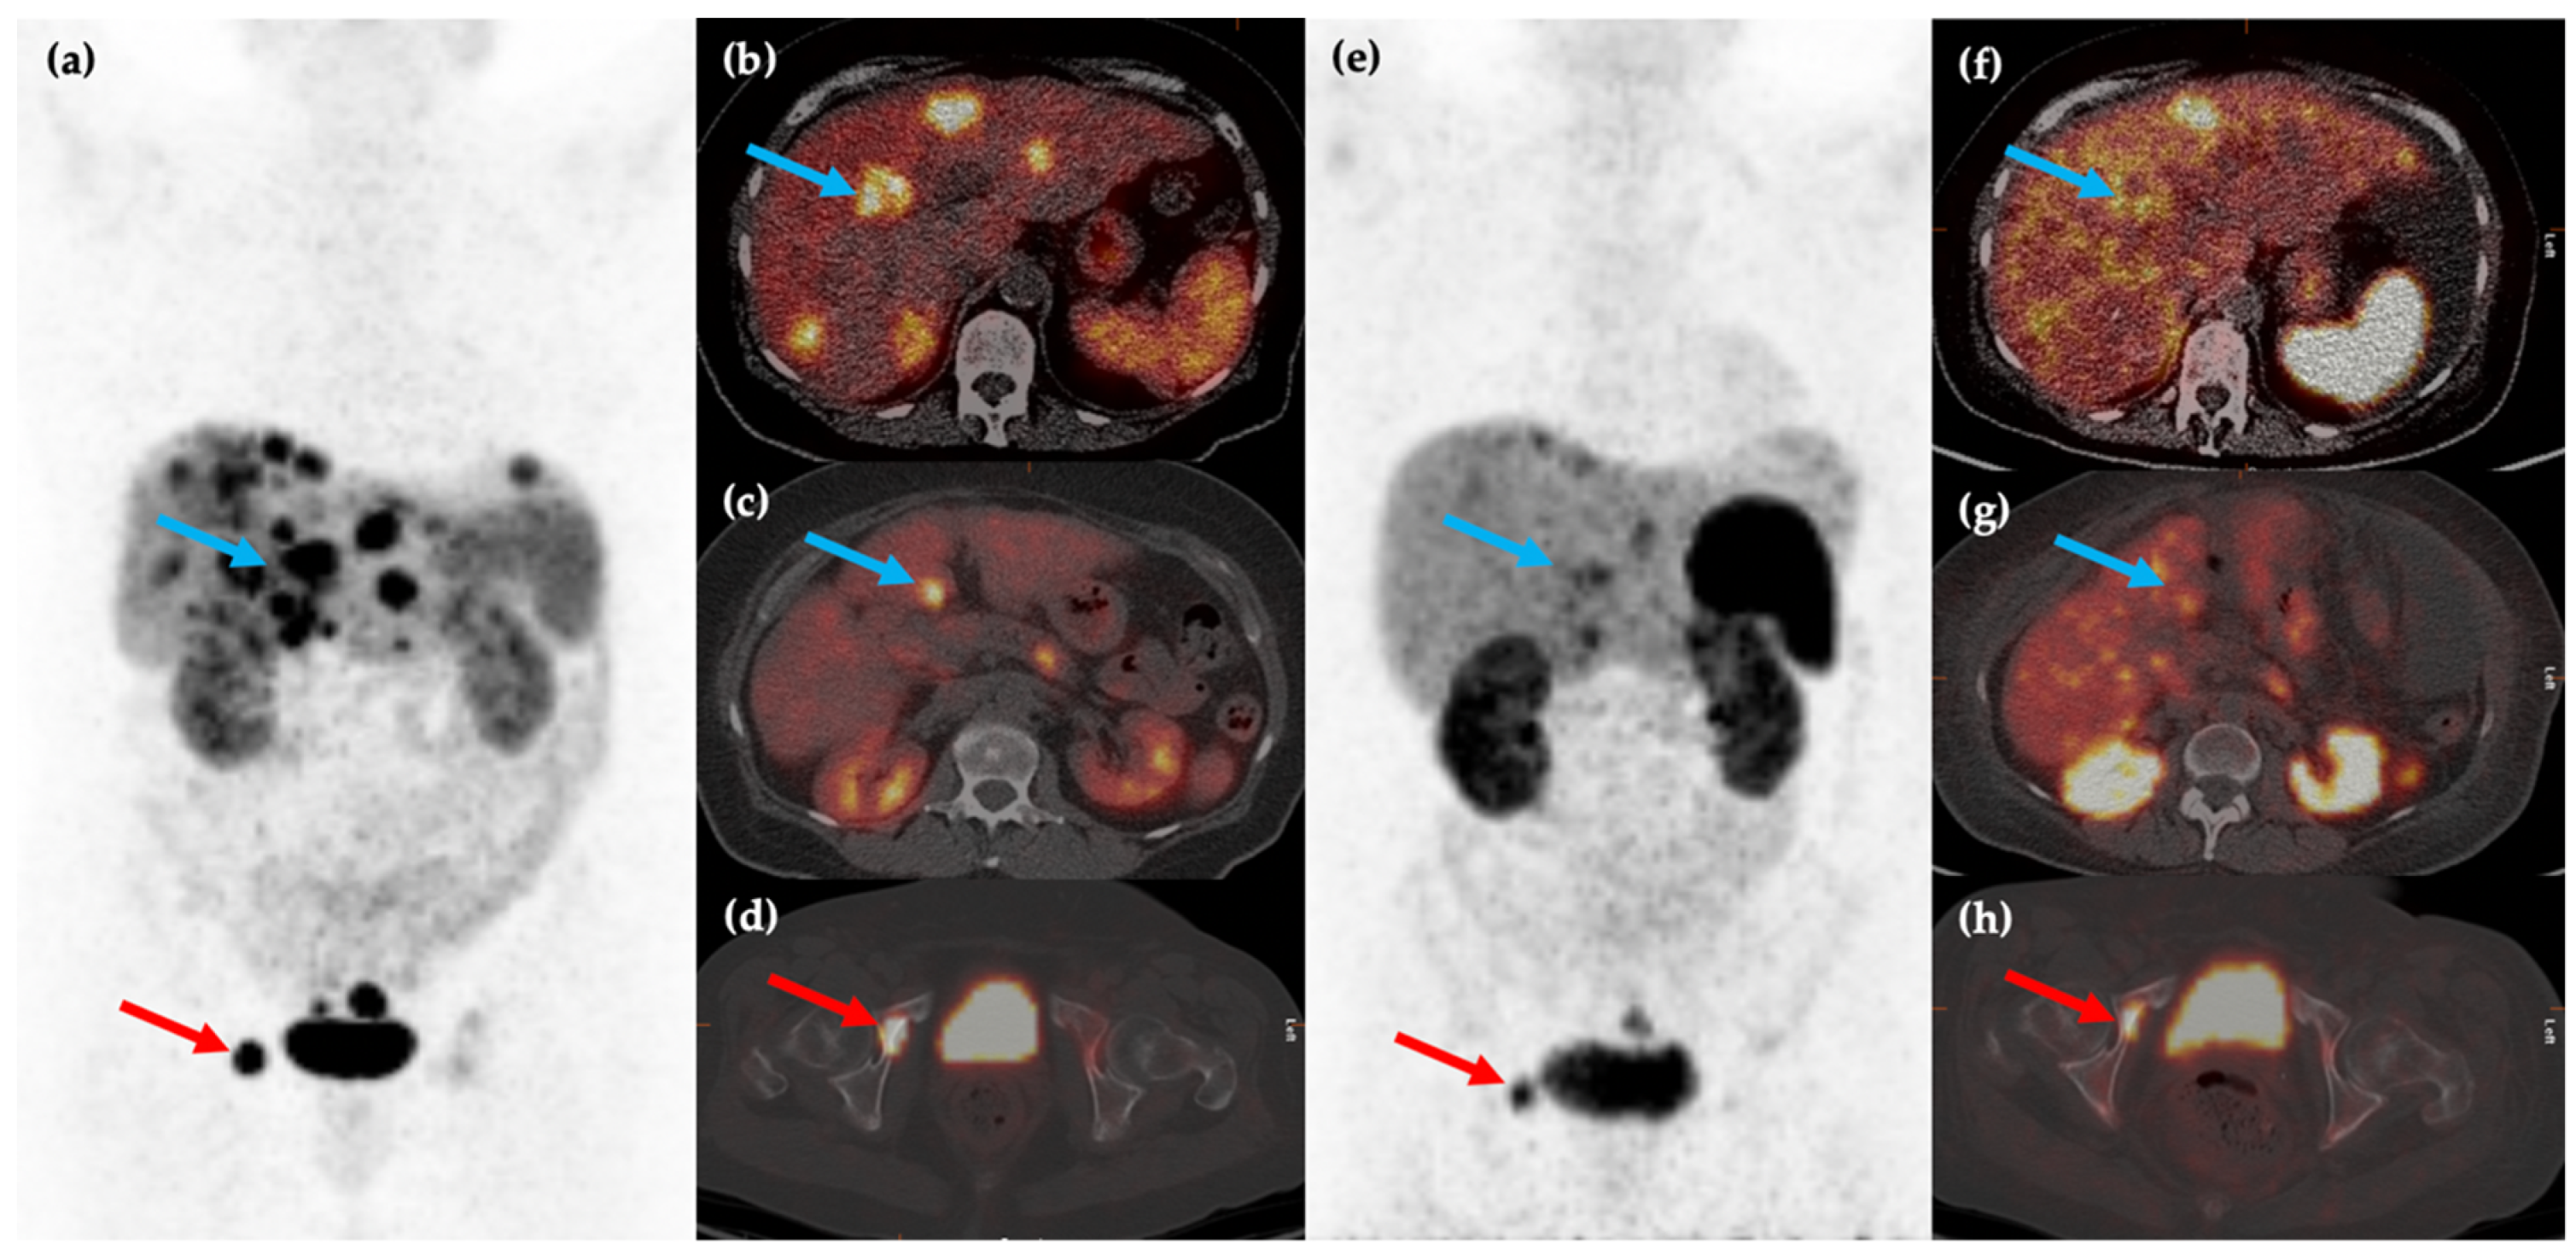

Figure 3.

Fifty-year-old female with metastatic G1 NET to liver and bones. 68Ga-DOTATATE PET/CT MIP (a) and axial (b–d) images show multiple sites of SSTR positive hepatic (blue arrows) and osseous (red arrows) disease. The patient was treated with 177Lu-DOTATATE with favorable partial response on post-therapy 68Ga-DOTATATE PET/CT MIP (e) and axial (f–h) images, which show reduction in size and/or number of the previous sites of disease.